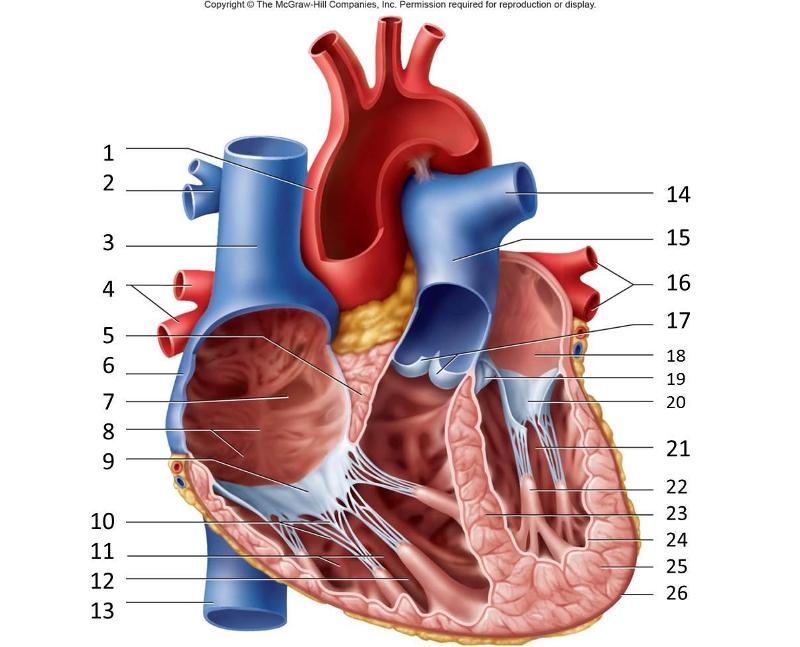

Anterior interventricular valve

Anterior interventricular sulcus

Posterior interventricular sulcus

Aortic Valve (=left semilunar)

Apex (of the heart)

Ascending/descending aorta

Brachiocephalic artery

Brachiocephalic vein

Chordae tendineae

Circumflex branch (of the left coronary artery)

Coronary sinus

Endocardium

Epicardium

interventricular branch of the left coronary artery. = left anterior descending artery (LADA))

Left atrioventricular (=bicuspid, =mitral) valve

Left/right atrium

Left/right auricle

Left/right coronary artery

left/right pulmonary artery/vein

left/right ventricle

Myocardium

Papillary muscles

Pectinate muscles

Pulmonary trunk

Pulmonary valve (=right semilunar)

Right atrioventricular (=tricuspid) valve

Superior/inferior vena cava